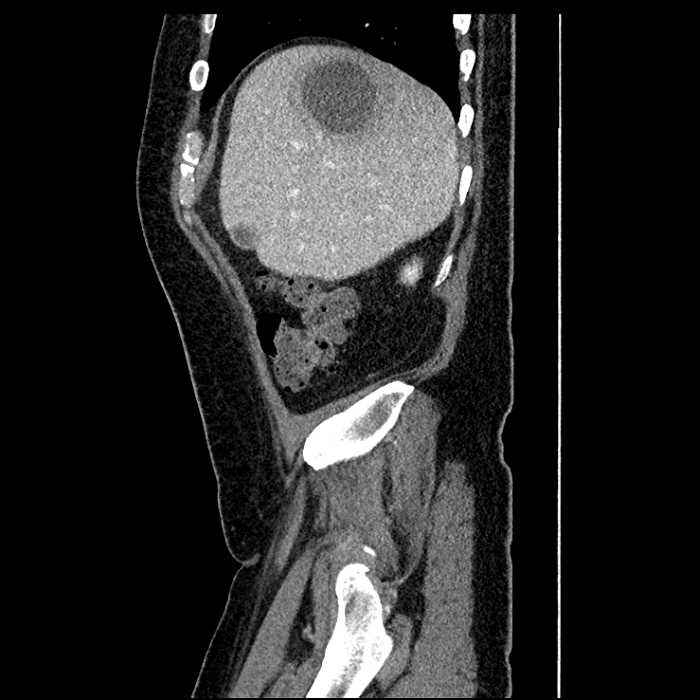

Age: 63

Sex: Male

Indication: Abdominal pain

• Large fluid density structure in hepatic segments 7 and 8 measuring 10 x 7 x 7 cm with internal septation and circumferential ill-defined low density compatible with edema

• Peripherally enhancing subcapsular collections along the anterior margin of the left hepatic lobe measuring 3 x 1 cm and 2 x 1 cm

• Clearly marginated fluid density structure in segment 7 and several other scattered tiny hypodensities, which likely represent cysts

Acute sigmoid diverticulitis complicated by a small contained perforation and a large abscess in the right hepatic lobe. Additional small subcapsular abscesses along the anterior margin of the left hepatic lobe.

• The classic CT imaging appearance is a double target sign with internal low density surrounded by an internal enhancing rim (capsule) and a low density external rim (edema)

Hepatic abscess showing the double target sign with low density internally surrounded by a thin inner enhancing rim (red arrow) and ill-defined outer low density rim (yellow arrow). Blue arrow indicates an internal septation. Red arrows: additional smaller subcapsular abscesses. Red arrow: focal contained perforation associated with diverticulitis.